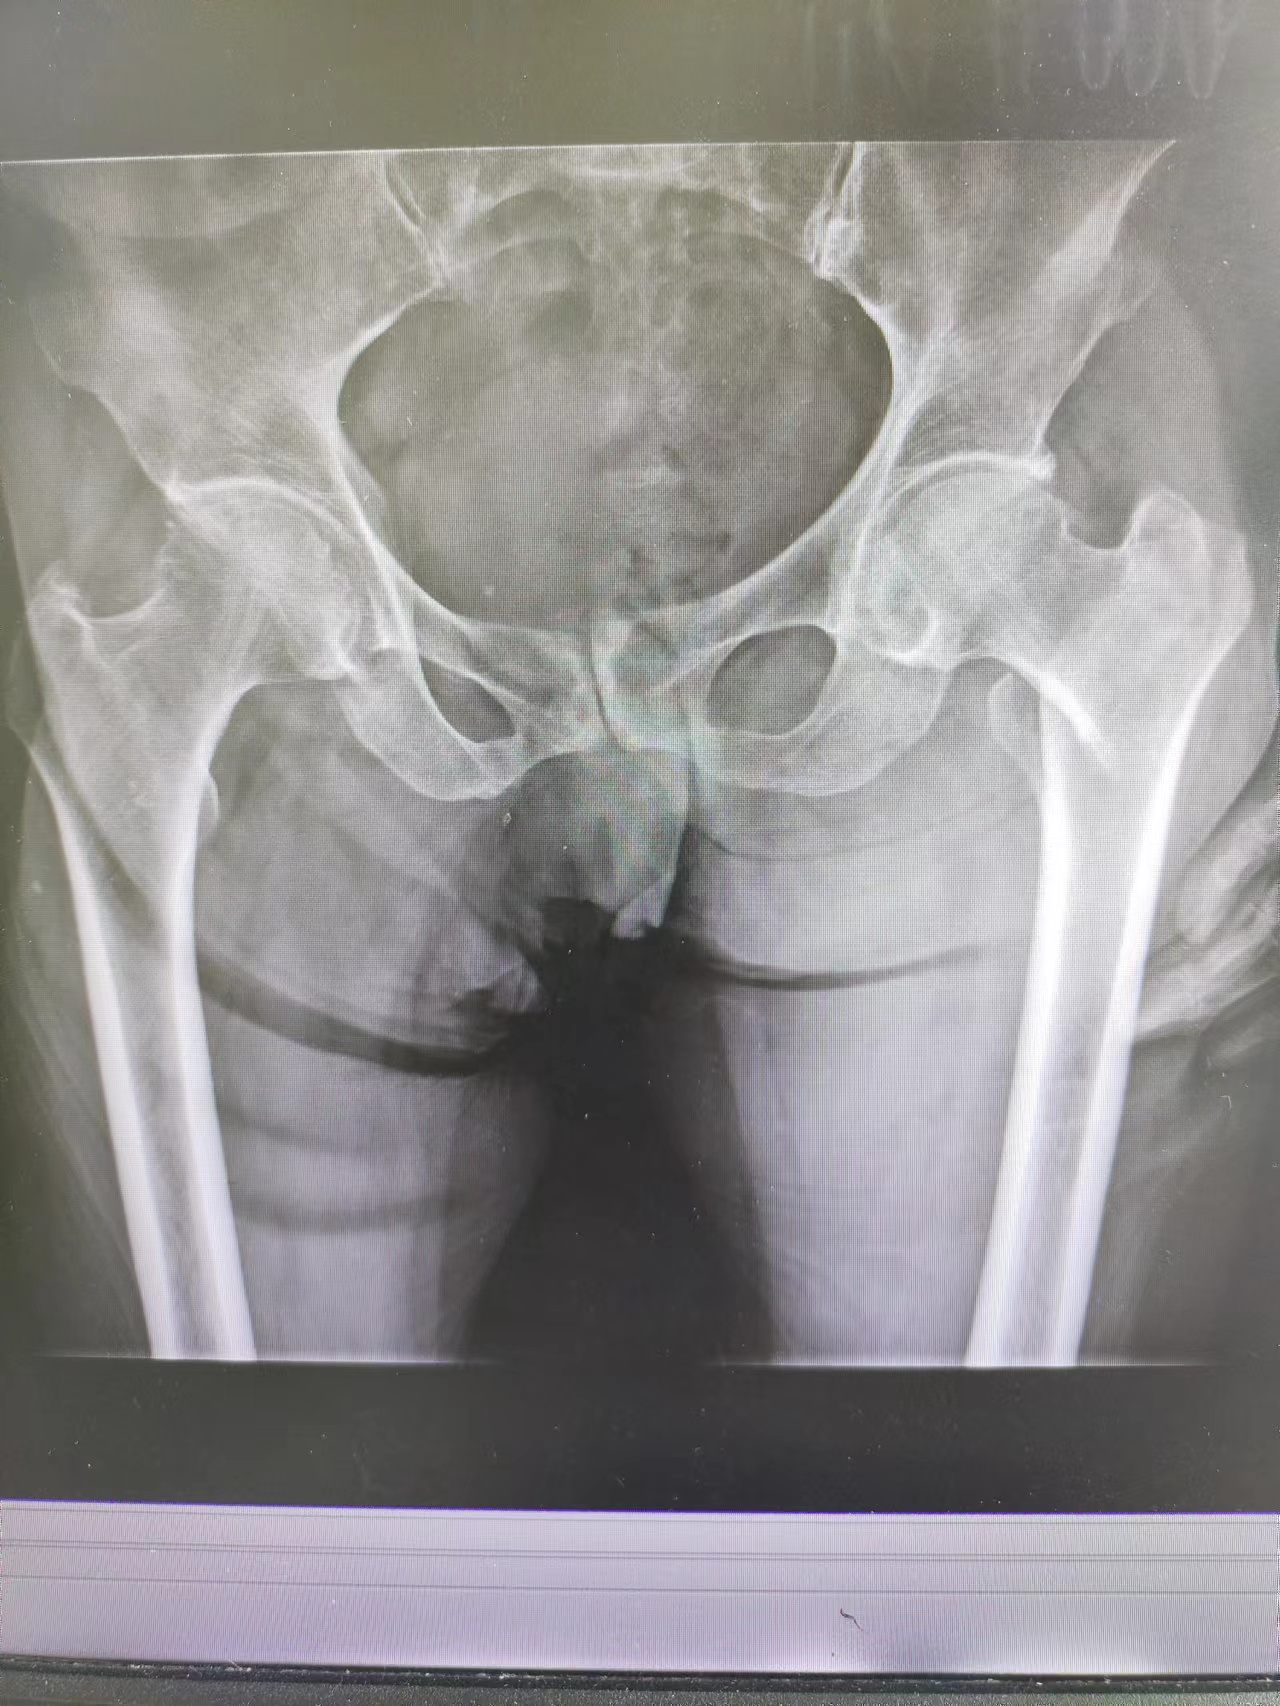

86、88、90、92、93、97、98,您以為這是一串考試成績(jī)嗎?不是,這是一個(gè)月內(nèi)我院關(guān)節(jié)外科、創(chuàng)傷骨科收治的10余名高齡患者的年齡,均為髖部骨折。通過(guò)關(guān)節(jié)外科、創(chuàng)傷骨科與麻醉科、心內(nèi)科、呼吸科、神經(jīng)內(nèi)科等兄弟科室的通力合作,均行手術(shù)治療,目前都已康復(fù)出院,戰(zhàn)勝了“人生最后一次骨折”,也獲得了患者家屬的高度贊譽(yù)。

臨床上,人生最后一次骨折,常常指的是老年人的髖關(guān)節(jié)骨折。由于骨質(zhì)疏松癥的發(fā)病率很高,根據(jù)資料統(tǒng)計(jì),男性一生中發(fā)生髖部骨折的風(fēng)險(xiǎn)高達(dá)11.2%,女性更高達(dá)23%。髖部骨折是對(duì)老年人影響最大的一類骨質(zhì)疏松骨折。不像那些發(fā)生在腕部或肩部的骨折,髖部骨折帶來(lái)的疼痛和下肢活動(dòng)障礙會(huì)迫使病人臥床,難以活動(dòng);而保守治療需要臥床三個(gè)月左右,而臥床帶來(lái)的四大并發(fā)癥,呼吸系統(tǒng)感染、泌尿系統(tǒng)感染、深靜脈血栓和褥瘡,哪一個(gè)發(fā)生了都會(huì)危及病人的生命。所以一旦發(fā)生髖部骨折,即使保守治療也會(huì)危險(xiǎn)重重,手術(shù)又有一定的風(fēng)險(xiǎn)。因此,髖部骨折在過(guò)去就被稱為“人生最后一次骨折”。手術(shù)治療可早期下地活動(dòng),但手術(shù)風(fēng)險(xiǎn)較高,存在心腦血管意外可能性較大。因此,術(shù)前需認(rèn)真進(jìn)行評(píng)估,盡可能降低手術(shù)風(fēng)險(xiǎn)。

隨著醫(yī)學(xué)技術(shù)的發(fā)展,髖部骨折手術(shù)治療已經(jīng)是比較成熟的手術(shù),高齡已不再是手術(shù)禁忌。老年人摔倒后應(yīng)積極就醫(yī),避免延誤最佳治療時(shí)機(jī)。